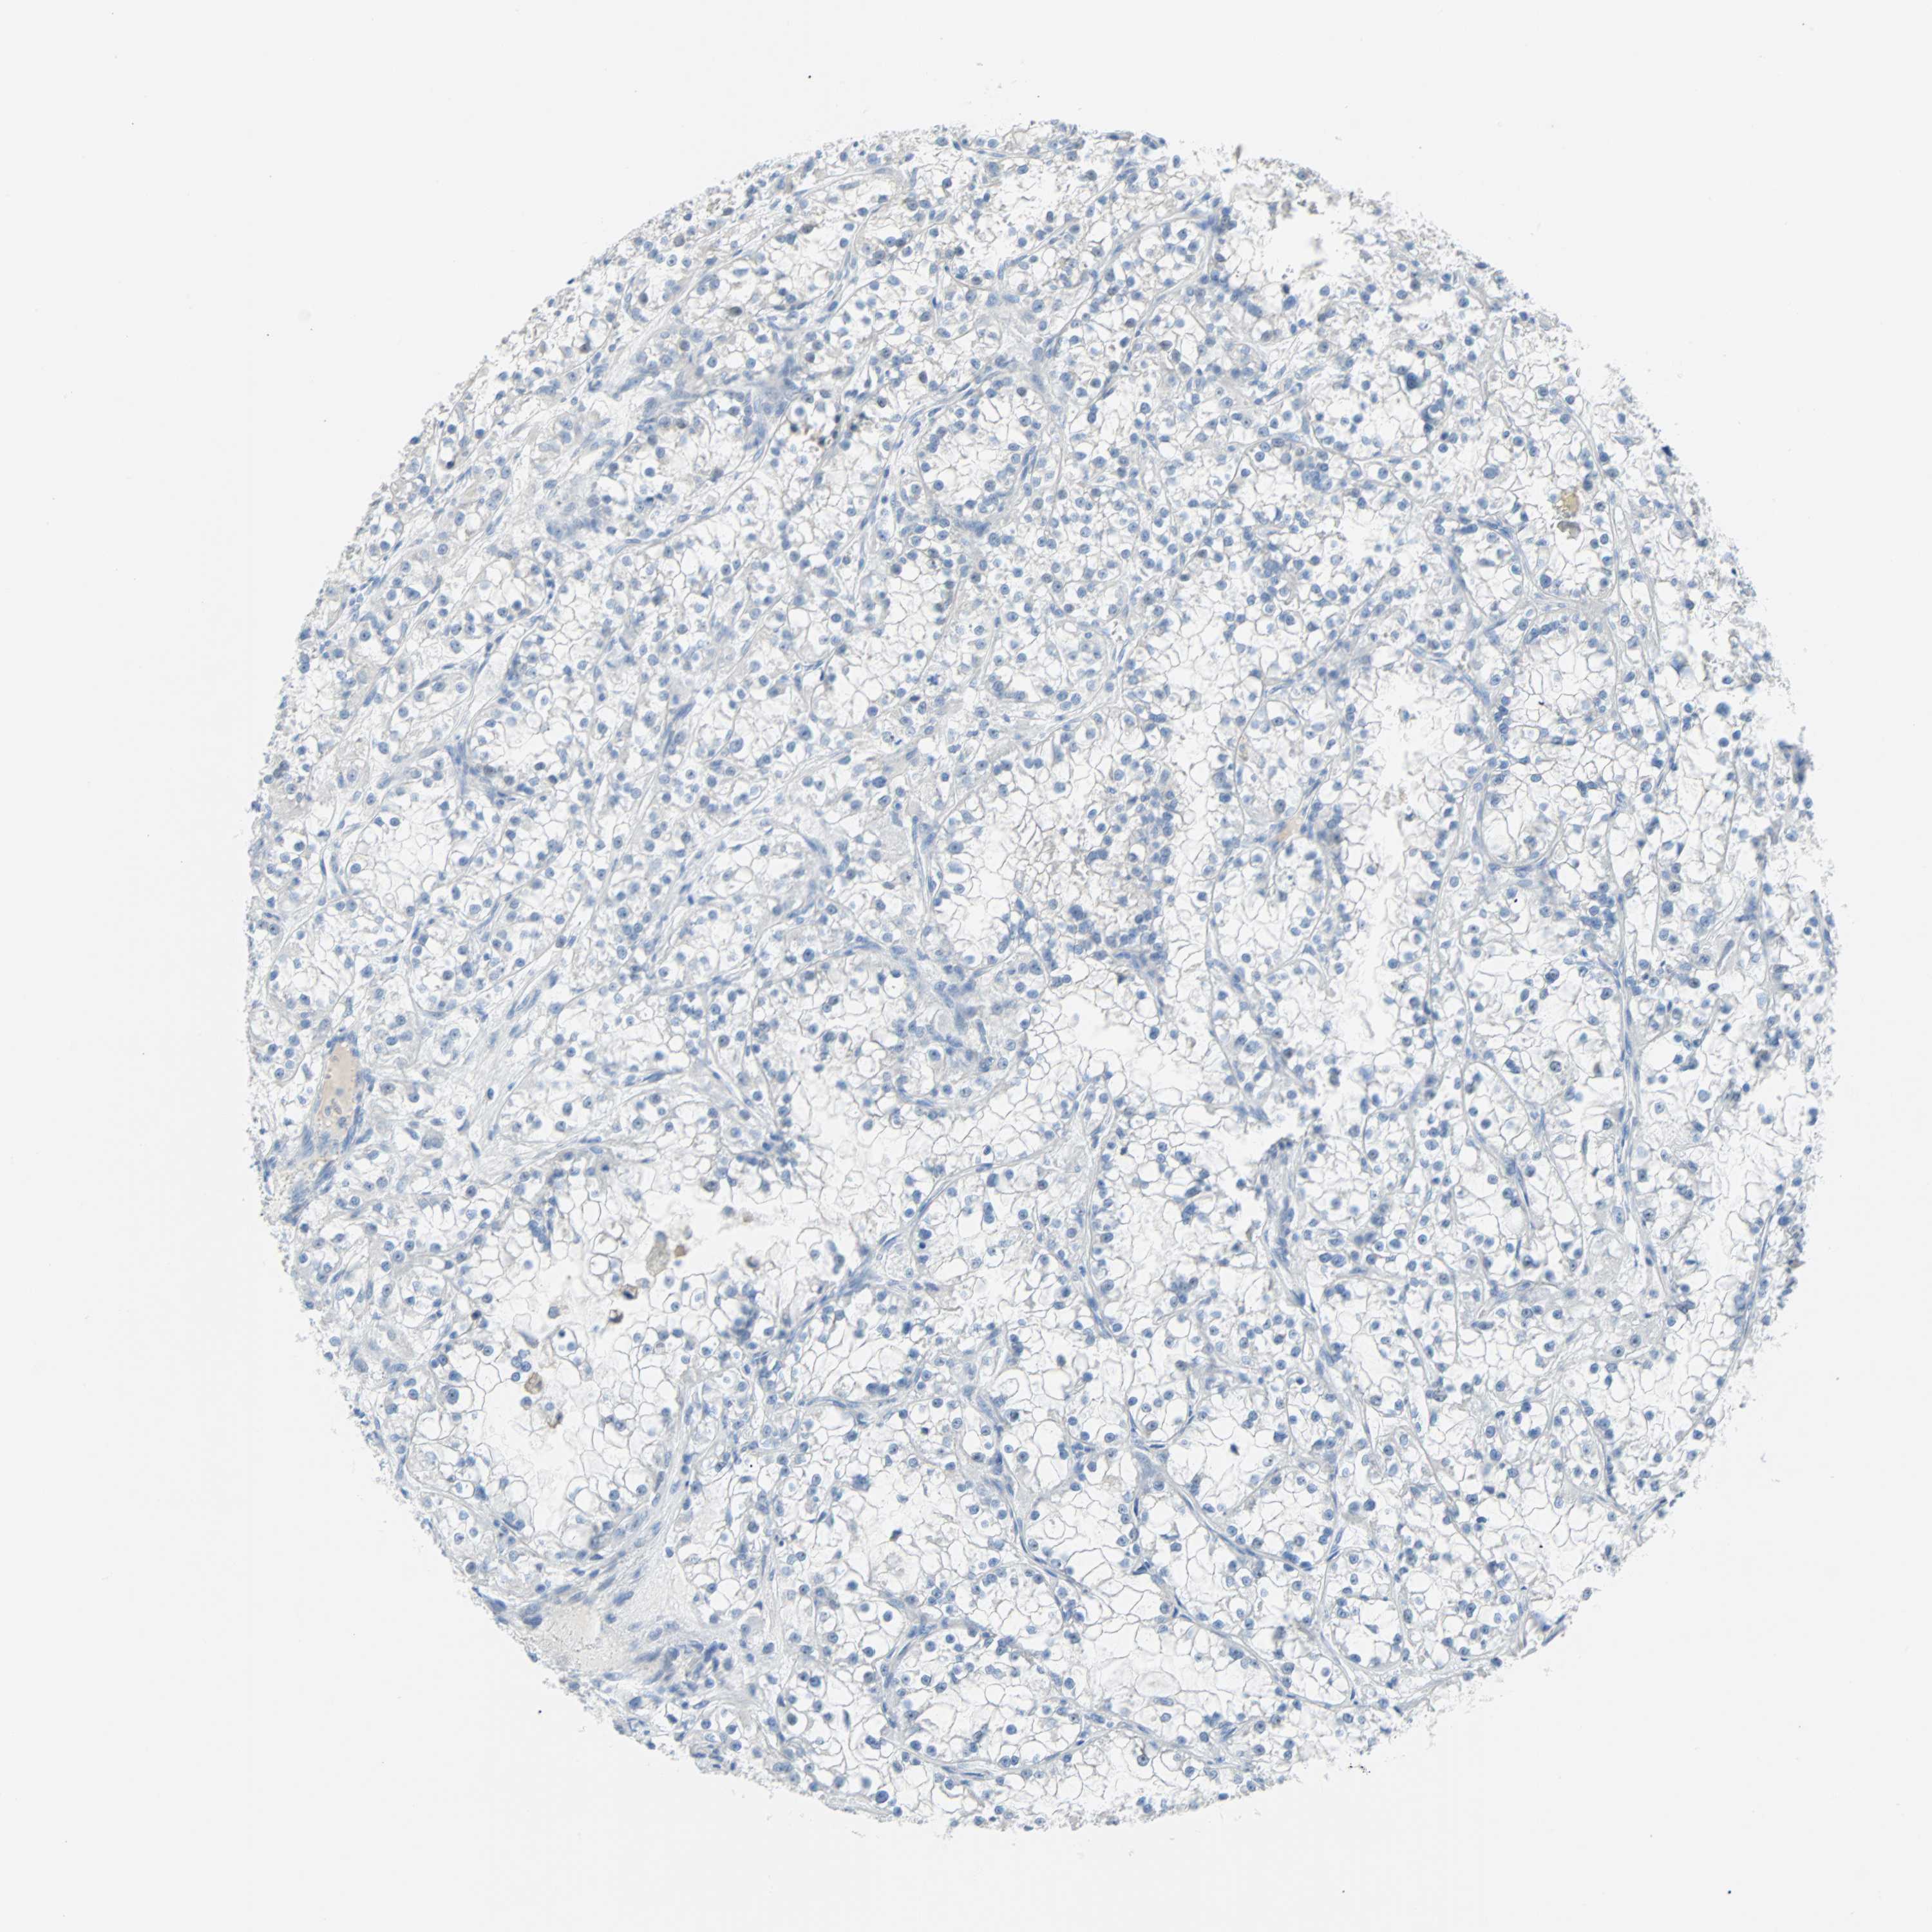

PDPN is not prognostic in Kidney Renal Papillary Cell Carcinoma (TCGA)